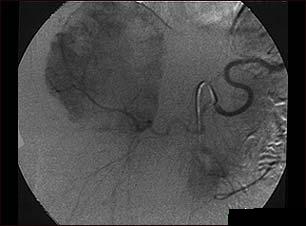

Hemangiomul hepatic